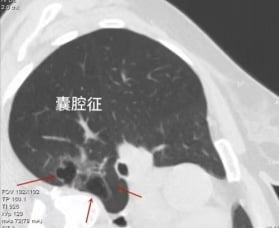

九、囊腔征:需与肺大泡鉴别的恶性病变

囊腔征的特征在于其内部空腔成分占据显著体积,远大于周围的有形成分,初次观察时极易与肺大泡混淆。然而,囊腔征的壁部明显增厚,且常常混杂有磨玻璃样成分,增厚在不同方向上呈现不均匀特点,这与典型的肺大泡薄壁形成鲜明对比。因此,尽管外观相似,但囊腔征是囊腔型肺癌的一种特殊表现。细致入微的观察与准确的鉴别诊断至关重要,以确保及时识别潜在的恶性肺结节。